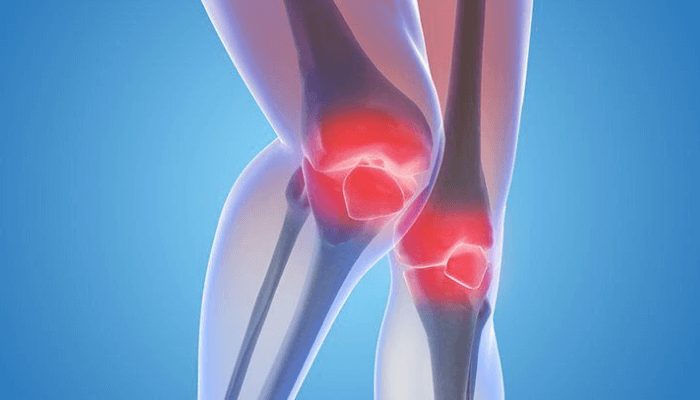

Ope had been diagnosed with arthritis two years ago, though the pain had begun much earlier. At first, it was just stiffness in his knees after a long day. But gradually, the pain intensified, and simple tasks like standing up, bending, or even gripping his favorite teacup became challenging.

Arthritis is an umbrella term for a group of diseases that cause inflammation and stiffness in the joints. In Nigeria, it is commonly associated with aging, but it doesn’t spare younger people. Many dismiss the early signs as “ordinary body pain,” often delaying diagnosis and worsening the condition.

For Ope, the diagnosis of osteoarthritis ‘this is a common form caused by wear and tear of the joints’ came with a mix of relief and dread. Finally, he had an explanation for his discomfort, but the doctor’s words echoed in his mind: “There is no cure, but there are ways to manage it.”